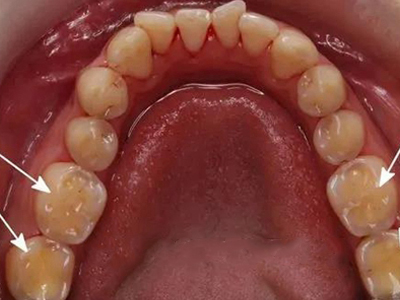

酸蚀症牙齿缺损有洞图

患酸蚀症时,牙齿可发生缺损,表现为牙列内侧有凹陷的坑洞形成,形状不规则,大小不一,坑洞处牙齿发黄,需积极控制病因,并进行充填修复治疗。

酸蚀症前牙面出现浅沟凹陷小坑图

酸蚀症患者的单个牙齿前面靠近牙龈处出现浅沟凹陷,表面有小坑,颜色与正常牙齿相比明显发黄,用手指触摸表面时会感到凹凸不平,牙齿较为敏感,易受到冷、酸等外界刺激。

酸蚀症牙齿内侧有凹坑发黄图

出现酸蚀症时,牙齿内侧会在腐蚀下形成凹陷的坑,大小不一,坑处牙齿表面发黄,形似茶渍。该病的发生可能与胃液反流,内源性酸性物质腐蚀牙面导致。